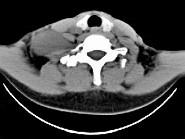

- 单项选择题女,47岁, 下颈部触及一包块约五年余,CT如图所示, 最可能诊断为  (    )

- A、滑膜肉瘤

- B、血管瘤

- C、神经鞘瘤

- D、副神经节瘤

- E、巨淋巴结增生症